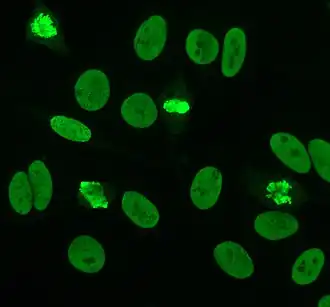

Indirect immunofluorescence is one of the most commonly used tests for ANAs. Typically, HEp-2 cells are used as a substrate to detect the antibodies in human serum. Microscope slides are coated with HEp-2 cells and the serum is incubated with the cells. If the said and targeted antibodies are present then they will bind to the antigens on the cells; in the case of ANAs, the antibodies will bind to the nucleus. These can be visualised by adding a fluorescent tagged (usually FITC or rhodopsin B) anti-human antibody that binds to the antibodies. The molecule will fluoresce when a specific wavelength of light shines on it, which can be seen under the microscope. Depending on the antibody present in the human serum and the localisation of the antigen in the cell, distinct patterns of fluorescence will be seen on the HEp-2 cells.[51][52] Levels of antibodies are analysed by performing dilutions on blood serum. An ANA test is considered positive if fluorescence is seen at a titre of 1:40/1:80. Higher titres are more clinically significant as low positives (≤1:160) are found in up to 20% of healthy individuals, especially the elderly. Only around 5% of the healthy population have ANA titres of 1:160 or higher.[8][53]

They are superior to the previously used animal tissues because of their large size and the high rate of mitosis (cell division) in the cell line. This allows the detection of antibodies to mitosis-specific antigens, such as centromere antibodies. They also allow identification of anti-Ro antibodies, because acetone is used for fixation of the cells (other fixatives can wash the antigen away).[56]

There are many nuclear staining patterns seen on HEp-2 cells: homogeneous, speckled, nucleolar, nuclear membranous, centromeric, nuclear dot and pleomorphic. The homogeneous pattern is seen when the condensed chromosomes and interphase chromatin stain. This pattern is associated with anti-dsDNA antibodies, antibodies to nucleosomal components, and anti-histone antibodies. There are two speckled patterns: fine and coarse. The fine speckled pattern has fine nuclear staining with unstained metaphase chromatin, which is associated with anti-Ro and anti-La antibodies. The coarse staining pattern has coarse granular nuclear staining, caused by anti-U1-RNP and anti-Sm antibodies. The nucleolar staining pattern is associated with many antibodies including anti-Scl-70, anti-PM-Scl, anti-fibrillarin and anti-Th/To. Nuclear membrane staining appears as a fluorescent ring around the cell nucleus and are produced by anti-gp210 and anti-p62 antibodies. The centromere pattern shows multiple nuclear dots in interphase and mitotic cells, corresponding to the number of chromosomes in the cell. Nuclear dot patterns show between 13 and 25 nuclear dots in interphase cells and are produced by anti-sp100 antibodies. Pleomorphic pattern is caused by antibodies to the proliferating cell nuclear antigen.[26][53][57][58] Indirect immunofluorescence has been shown to be slightly superior compared to ELISA in detection of ANA from HEp-2 cells.[54]